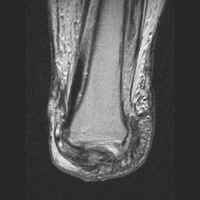

The MRI images below demonstrate the level of the Symes amputation along with bony and

soft tissue changes. Note the thick heel pad forming the majority of the distal

stump: the principle advantage of this procedure due to the more effective weight bearing.